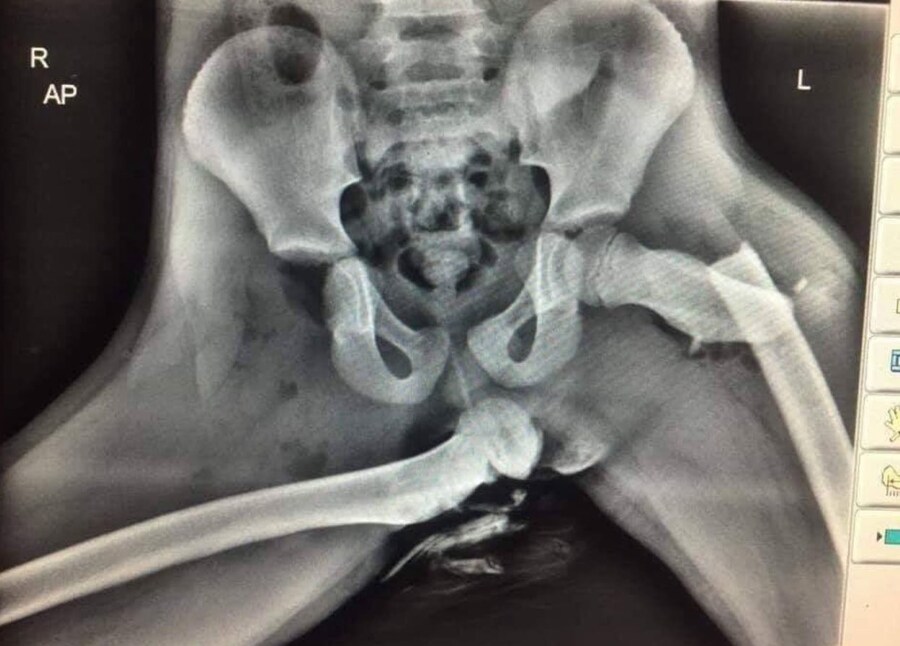

[유머] 자동차 대시보드에 다리를 올리면 안 되는 이유 (약혐주의) [37]

와 고관절 위치 ㄹㅇ 호러다..

복합골절인거 같은데 허벅지 복합골절이면 죽을 수도 있음

교통사고 나면 자력으로 탈출할 수 없는 이유

저건 못걷는건 당연하고 휠체어도 못타겠는데